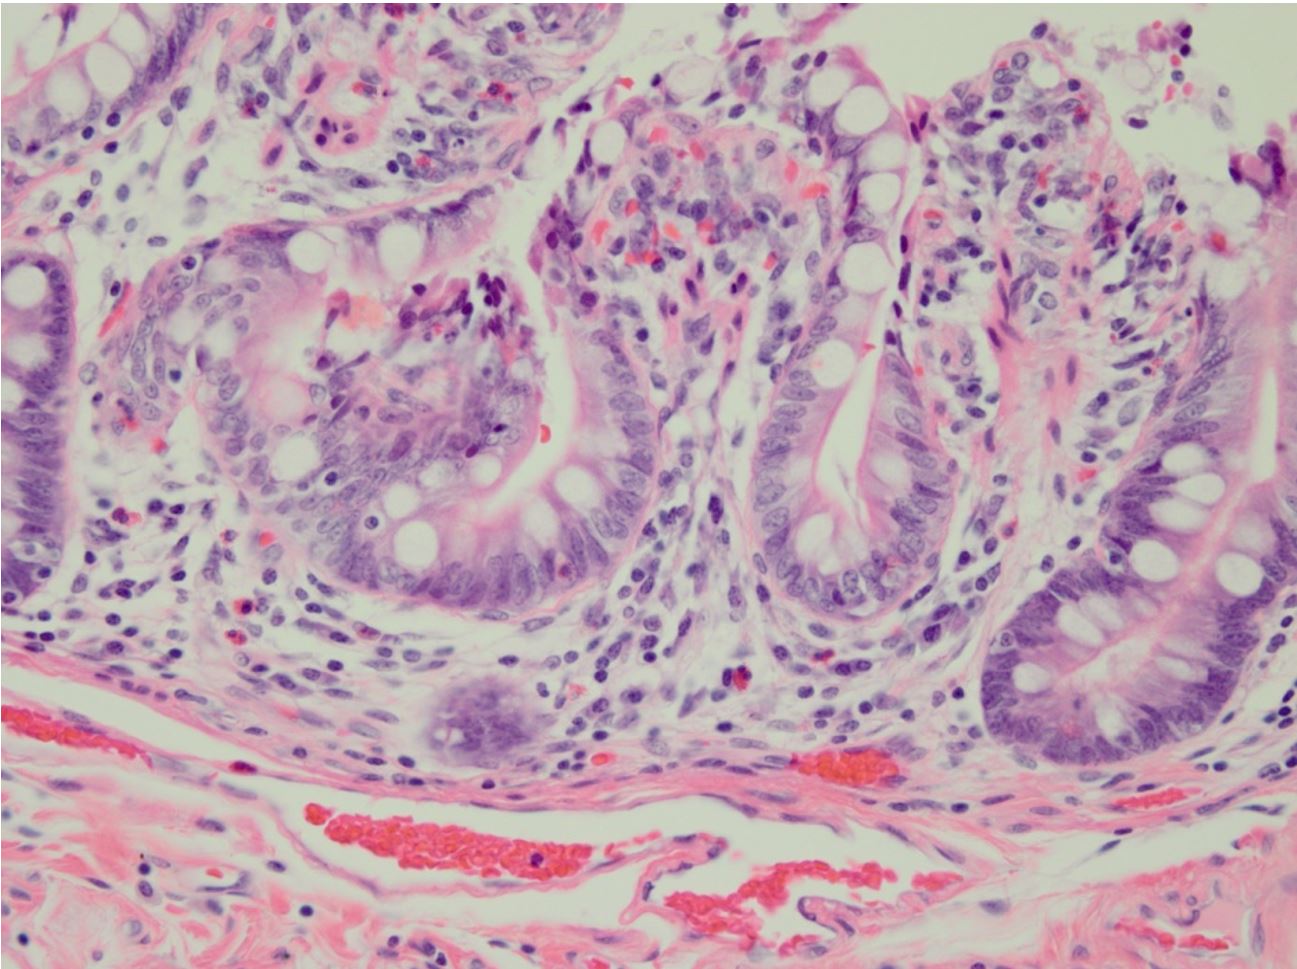

Pathologist: “Now, can you see that this slide from today is very pale? The nuclei are stained a faint blue and you can’t see nuclear detail. The eosin appears washed out. This is an awfully bad slide, and I cannot make a diagnosis from it.”